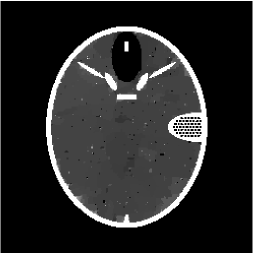

Figures 4 and 5 present visual reconstruction results of the SL phantom and the FB phantom, respectively, both under high additive Gaussian noise (). In particular, Figure 4 is to recover the SL phantom using 7 radial lines. The model has severe streaking artifacts due to this extremely small number of data obtained on the radial lines. The minimization on the gradient yields significant improvements over the baseline model (TV). The proposed algorithm outperforms the previous ADMM approach at the outer ring and boundaries of the three middle oval shapes, which are more obvious in the difference map to the ground truth. On the other hand, the FB phantom has finer structures and lower image contrast compared to the SL phantom. As a result, it requires 13 radial lines for a reasonable reconstruction. As we observe in Figure 5, the overall geometric shapes are preserved. At the same time, many speckle artifacts appear in the reconstructed images by no matter which algorithm is used.